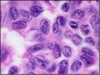

A patient has a gastric antral biopsy for abdominal pain, the slide of which is pictured. How does this organism survive in the acidic stomach?

A. Ammonia production

B. Hydroxide production

C. Bicarbonate production

D. Sulfate production

A. Ammonia production

H. pylori has a urase, which converts urea and water to CO2 and ammonia, which neutralizes gastric acid.